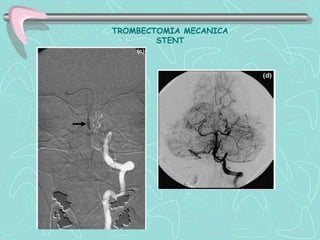

TROMBECTOMIA MECANICA

STENT